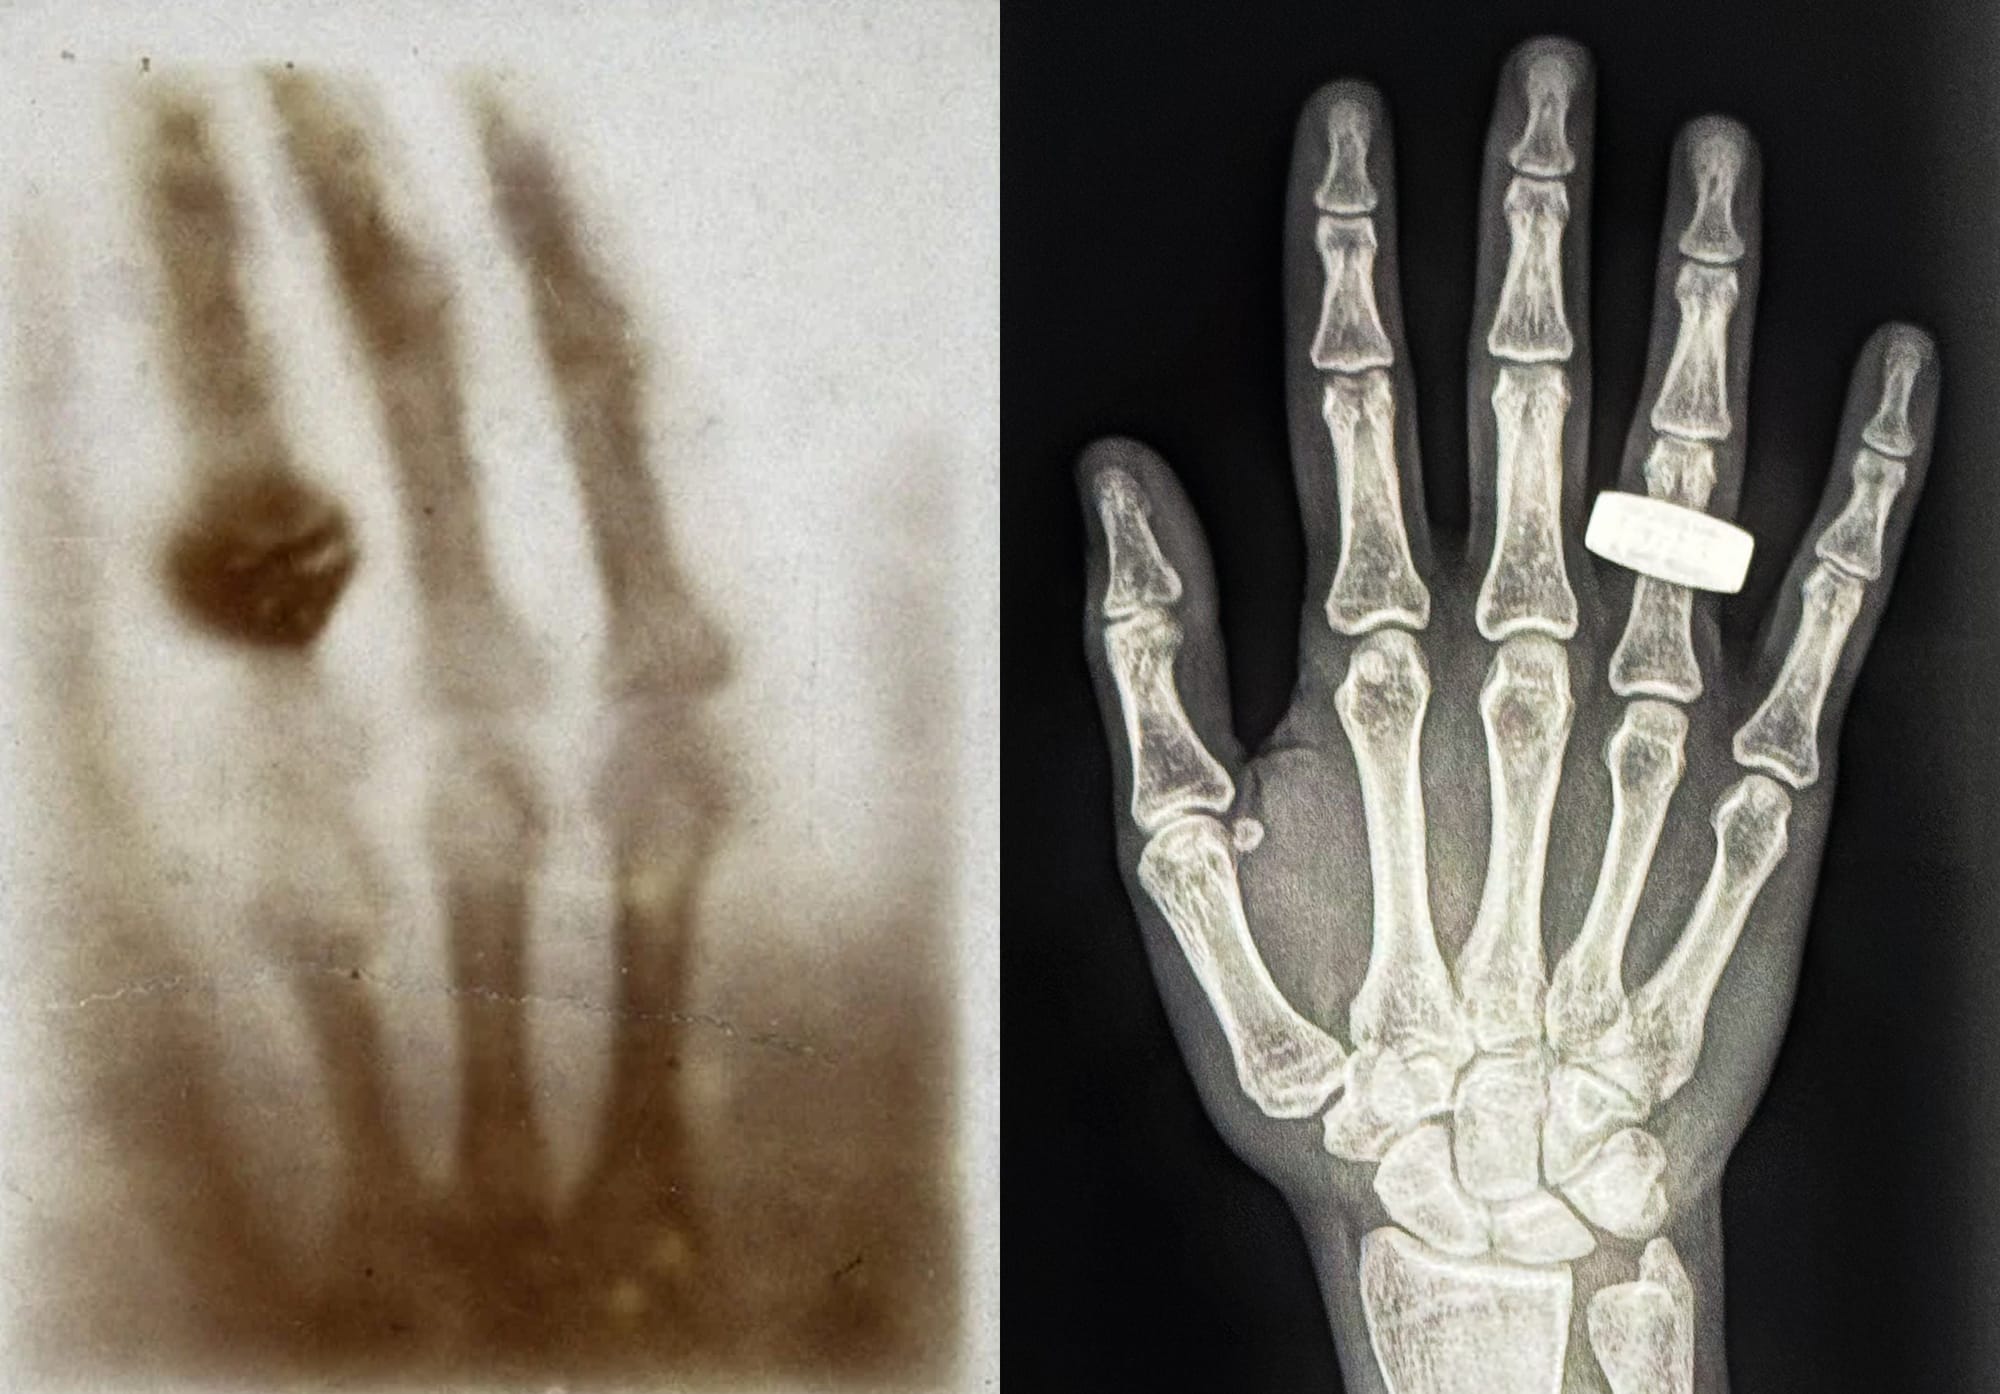

During their time in orbit, the crew conducted the world's first X-ray in orbit on a human. Alongside that, other experiments performed were exercise studies to maintain muscle and skeletal mass, along with growing mushrooms in microgravity.

- SpaceXray to capture the first human X-rays in space, paving the way for new clinical and research advancements.